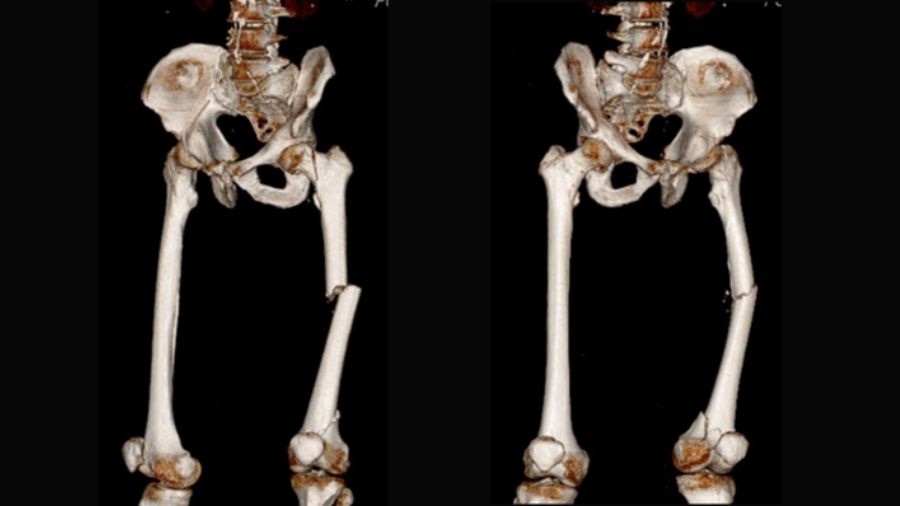

The trifocal femoral fracture (Figure 1) was classified as an obliquely oriented transcervical femoral neck fracture (AO/OTA 31-B2), a displaced shaft fracture (AO/OTA 32-A2), and a supracondylar fracture with intra-articular extension (AO/OTA 33-C2).